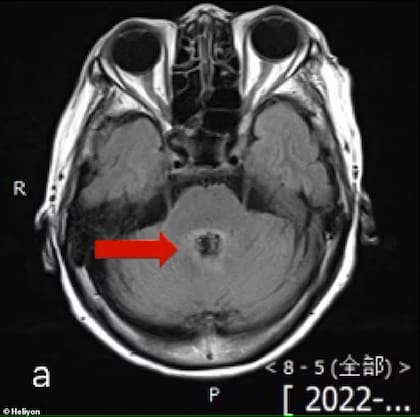

Hace días se convirtió en viral la historia de una mujer que puso en alerta a las comunidades rurales por un parásito potencialmente letal que ingresaría al cuerpo humano, se instalaría en el cerebro y produciría una muerte dolorosa. La paciente, de origen chino cuyo nombre se mantuvo en el anonimato, murió luego de que los médicos confundieran un tumor en su cabeza con una “ameba come cerebros”.

Según detalló el medio citado, la mujer asistió al hospital porque tenía dolor de cabeza, mareos, confusión y dificultad para hablar. En un estudio preliminar por resonancia, los médicos determinaron que tenía cáncer, en particular por la lesión en el cerebro que era evidente. Sin embargo, a los pocos días le realizaron una punción lumbar -para extraer líquido necesario para analizar- y el resultado fue mucho más angustiante.

La mujer estaba infectada con la ameba Balamuthia mandrillaris, que se instala en el cerebro y se alimenta de este. El nombre propio de la enfermedad se denomina encefalitis granulomatosa amebiana y cuatro tipos de ellas pueden ser letales.